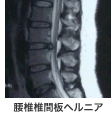

といった症状があった場合、腰椎疾患を疑う必要があります。それら疾患の中には腰部脊柱管狭窄症、腰椎椎間板ヘルニア、腰椎椎間板症、腰椎分離すべり症などがあります。